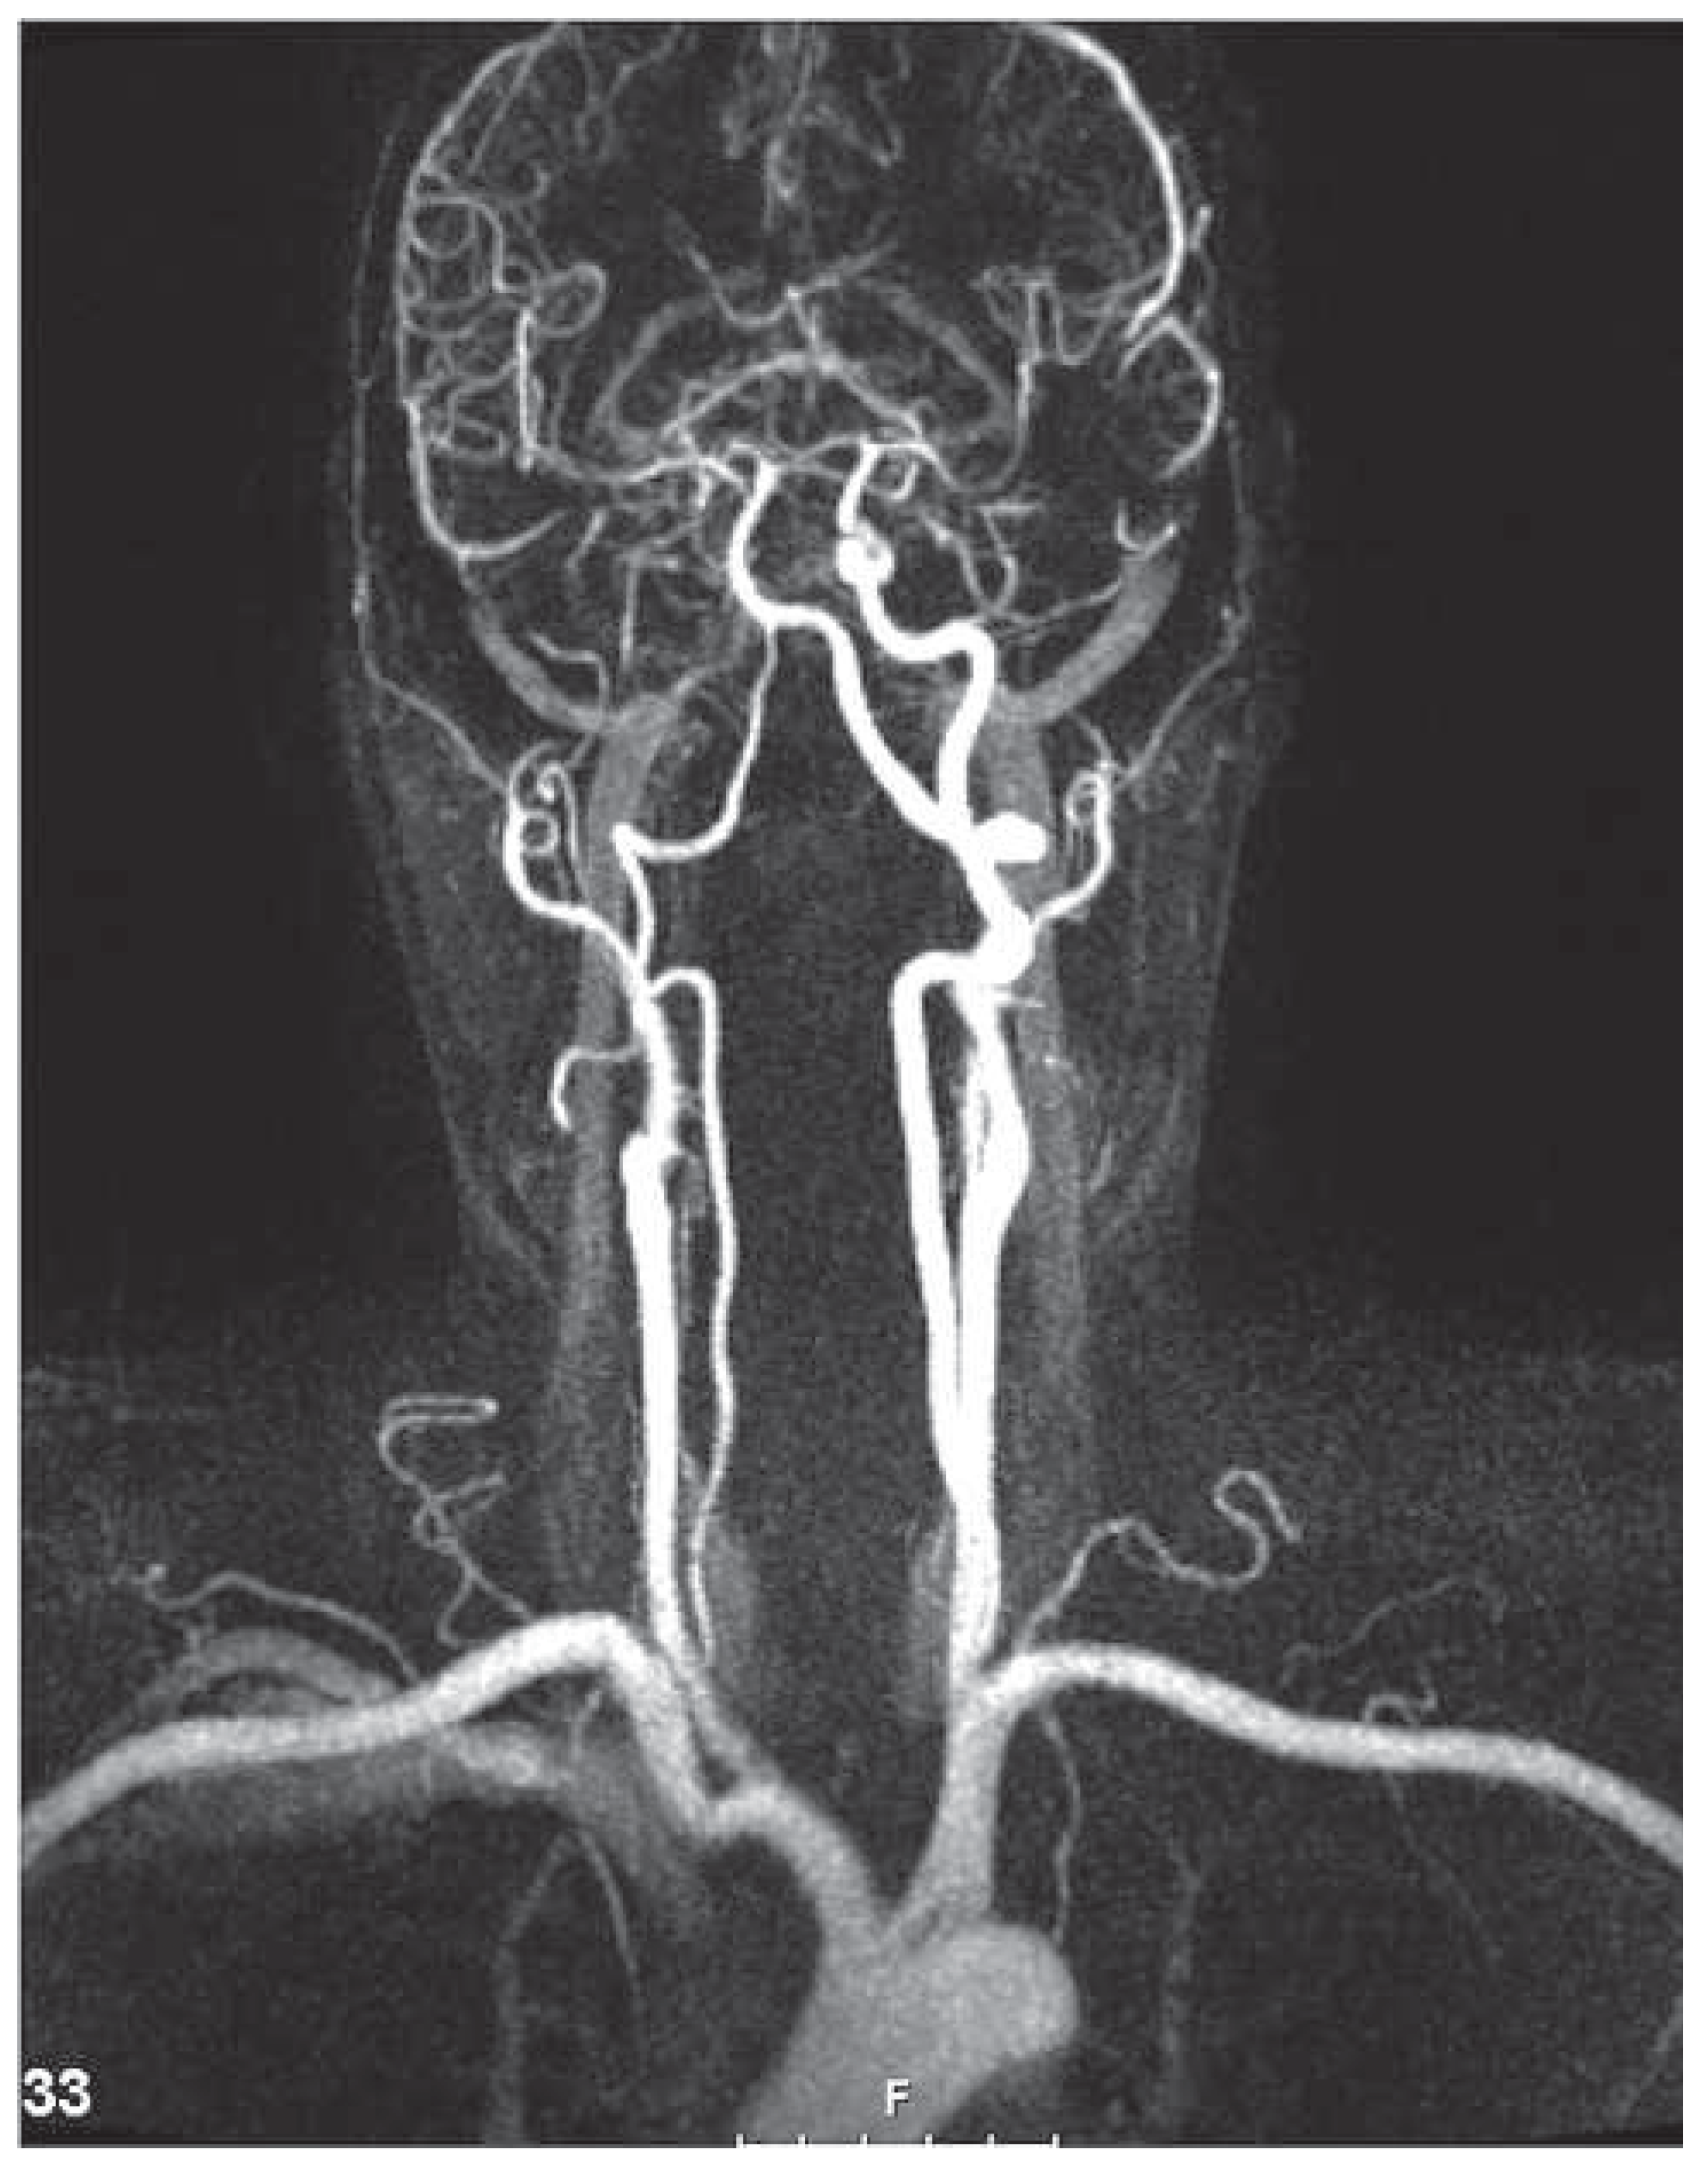

Case report